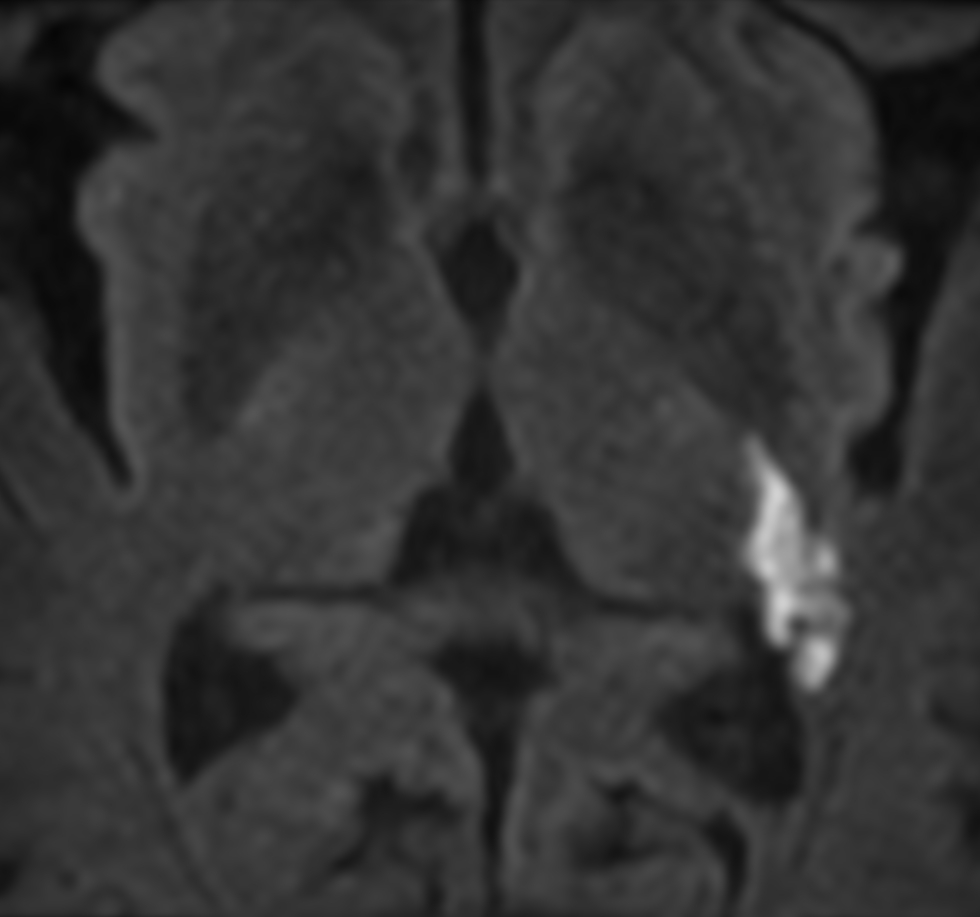

3D VIEW - T1w TFE (coronal reformat)